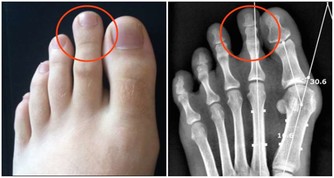

對於隱睾我們要做到三早:

1、早發現。

男孩父母在為孩子洗澡、換尿不濕情況時要注意觀察陰囊內是否有睾丸,兩邊大小是否一樣。

如果發現異常要及早到醫院就診。

2、早診斷。

當發現睾丸異常時要及時來醫院進一步檢查,隱睾是可以隱藏在腹腔、腹股溝管內環等處。

目前超聲檢查是最簡便,快捷無創的檢查方法,它不僅可檢查隱睾所在的位置,還可測量隱睾大小。

3、早治療。

隱睾的治療最好在2歲前完成。

新生兒發現隱睾可以定期觀察是否自下降行至陰囊內,對出生6個月後時睾丸還未降至陰囊內,則可考慮激素或手術治療。

對於青春期隱睾患者,一經發現及時行睾丸下降固定術,術中如發現睾丸已萎縮或不能下降引入陰囊,必要時可施行睾丸切除術。